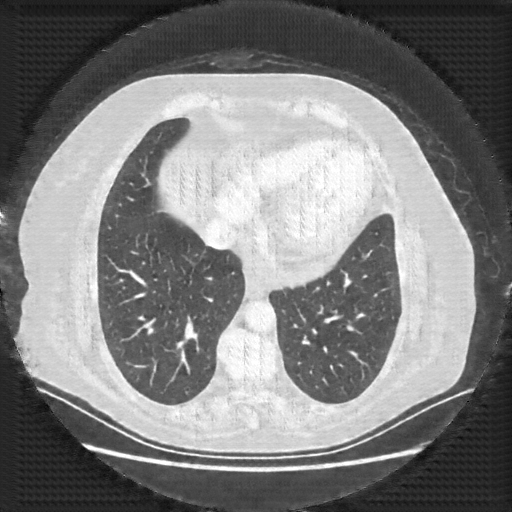

Original NATIVE CT scan (input)

Lung window (WL -600, WW 1500 β†’ Low βˆ’1350, High +150)

Reconstructed NATIVE CT scan (cycle consistency)

Original VENOUS CT scan

Generated VENOUS CT scan (A→B translation)